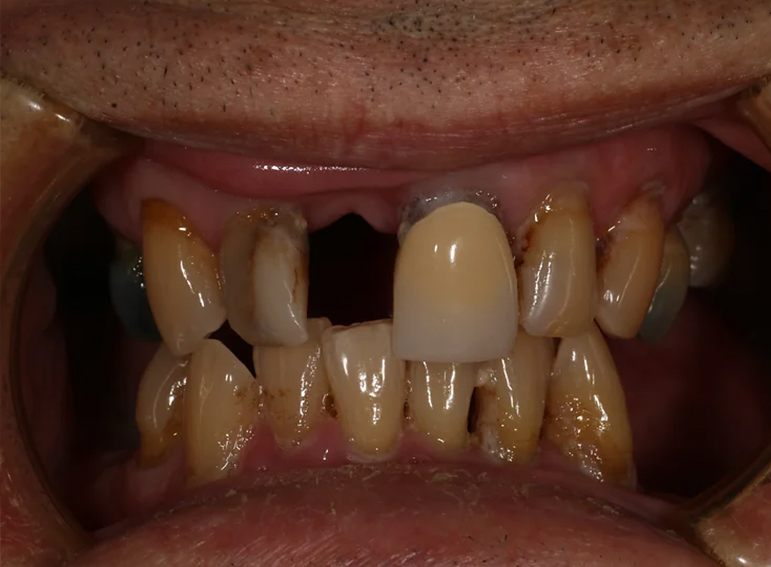

Complex upper and lower denture after oral cancer.